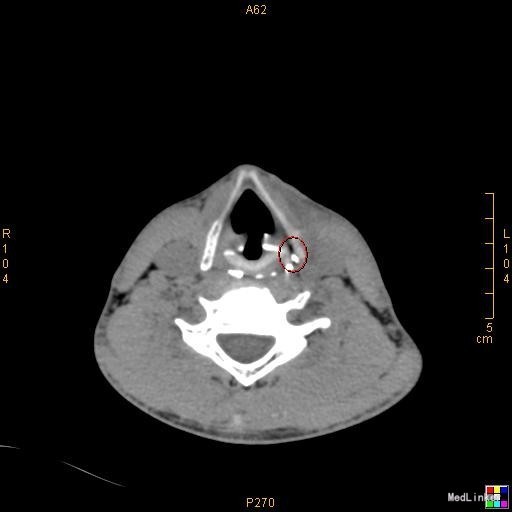

该患者在诊断上是有些困难,颈部多发脓肿是明确的,但是瘘口的位置不好确定,从而未能确诊,8年前患者行上消化道钡餐检查,诊断“食管瘘”,但是我们从8年前的影像上看,瘘口的位置太高,不像是食管的瘘口,考虑是不是梨状窝的瘘道,为了进一步确诊,我们给患者行了胃镜检查,结果胃镜发现左侧梨状窝有1个3mm大小的小孔,胃镜未能通过,食管未见明显的瘘口。为了更加明确瘘口的位置,我们与影像科商议后决定口服造影剂后行颈部CT平扫,因怕钡餐沉积在脓肿内不好排出,我们采用了口服碘化油。此次影像明确了瘘口的确在左侧梨状窝。最终诊断:左侧颈部多发脓肿;左侧梨状窝瘘道形成。 治疗:入院后予抗感染、禁食、营养支持等治疗,患者感染得以控制,请耳鼻咽喉科会诊后建议转科治疗。